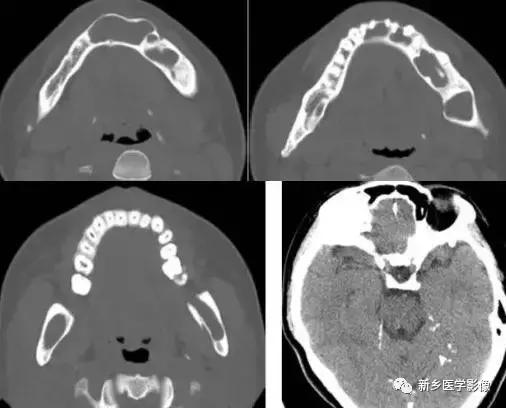

十四、基底细胞痣综合征

颅内可发生钙化,常位于大脑镰及小脑幕,也可发生于脑实质内。